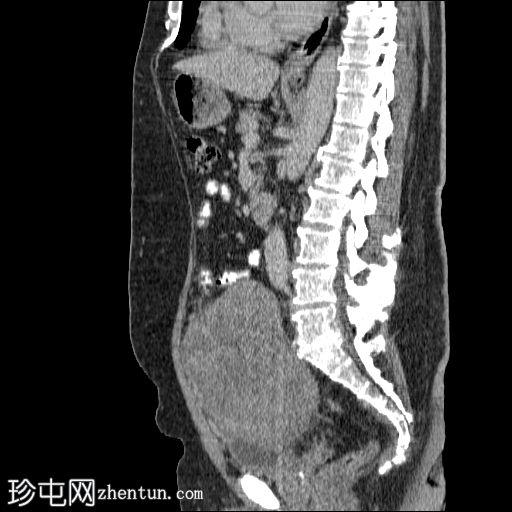

矢状位增强扫描(门静脉期)

盆腔内可见一大小为12 x 17 cm的边界清晰的异质性软组织肿块,向下延伸至下腹部。肿块内未见钙化或脂肪密度影。肿块向下推挤膀胱,并牵拉周围肠袢,但无放射学侵犯证据。未见明显淋巴结肿大、腹水或气腹。未见肺部或骨骼局灶性病变。肝脏可见数个小的单纯性囊肿。患者存在少量Bosniak I型肾囊肿,双侧肾盂肾盏系统饱满。曾行胆囊切除术。